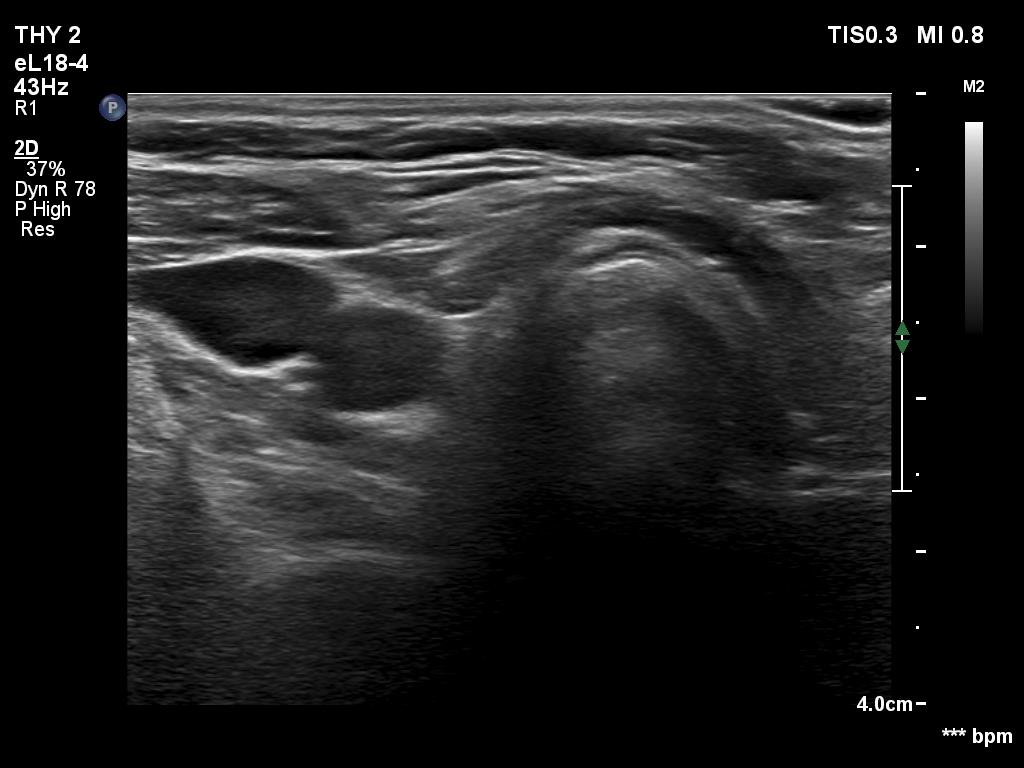

One year after the surgery (second row of images):

Clinical data: On routine follow-up, the surgeon palpated a mass in the middle of the neck. The patient was referred for evaluation and cytology of the mass.

Palpation: a not firm mass in the middle of the neck above the level of the thyroid.

Laboratory tests: TSH 3.01 mIU/L on daily 75 microgram levothyroxine.

Ultrasonography. Connective tissue replaced the thyroid. Approximately 4 cm above the level of the thyroid, a hypoechoic mass was found. The echo structure was identical to the that of the thyroid seen before the surgery.

Cytology was performed form the mass and resulted in benign hormonal atypia. Wash-out thyroglobulin exceeded 10,000 pg/mL.

Comment. The palpation remains a crucial examination in thyroid patients. If we did not palpate the neck, this lesion would be very likely overlooked on ultrasonography because of the similarity of the echo structure to the neighboring muscle tissue. The two types of tissue differed in two things, the thyroid gland contained less thick and shiny connective tissue bundles, and circulation was detected in it.